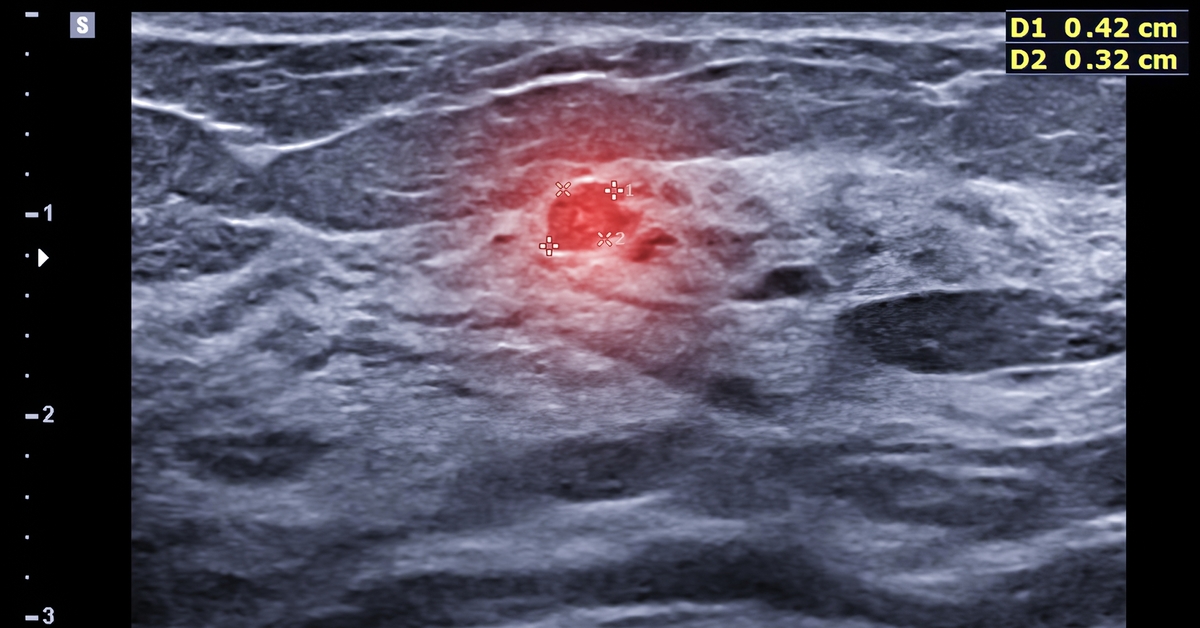

Hiçbir şikayet yaşamamasına rağmen erken teşhis sayesinde meme kanserine yakalandığını öğrenen Kapan, “Aile hekimim, Sincan Sağlıklı Hayat Merkezi (SHM) KETEM birimine randevu oluşturmayı teklif etmiş ancak acelem olduğu için sadece ilaç yazdırmaya geldiğimi söylemiştim. Randevuya pek sıcak bakmamama rağmen aile hekimim bu taramanın yapılmasının yararlarını ve gerekliliğini anlatarak randevumu oluşturdu. Sağlıklı Hayat Merkezine gittim ve hem mamografi çektirdim hem de serviks kanseri taraması için HPV numunesi verdim. Mamografi sonucum ‘BIRADS 4 Şüpheli Bulgular (Hastaneye Sevk)’ şeklinde geldi ve ileri teşhis merkezlerinden biri olan Abdurrahman Yurtaslan Onkoloji Eğitim ve Araştırma Hastanesine sevk edildim. Biyopsi sonucunda da 1. evre meme kanseri olduğum ortaya çıktı” dedi.